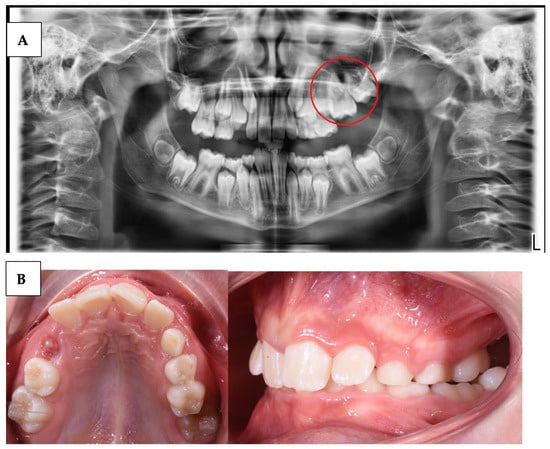

| Wagner et al. (2023) [59] | Case series | 3 | Describe the variability of clinical presentations of PFE associated with pathogenic variants of PTHR1 | Clinical examination, radiological examination, and molecular DNA testing | Multidisciplinary complex treatment, from child to adulthood. |